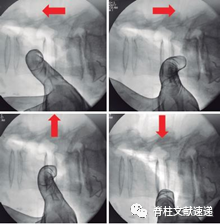

管状牵开器应放置在倾斜解剖入路上,牵开器的顶点应位于椎间盘的中心。要做到这一点,定位针的位置应该正确。

建议最初定位针应该在另一只手的食指保护下进入,避免在其放置过程中损伤结构。识别椎间隙并区分椎间盘和椎体结构时,应始终使用保护定位针的食指进行触诊,这样就可以避免腰椎节段动脉的任何潜在撕裂伤。侧位透视时应将针头插入椎间隙前三分之一与中间三分之一的交界处。

这一建议有助于管状牵开器的倾斜放置,也可以帮助保持cage的垂直放置。侧位和正位的透视保证了管状牵开器放置的安全性。在这一步骤中,直视是必要的;由于对输尿管、交感神经链或血管结构有潜在危险,管状牵开器下不应留下任何结构。

图示:在定位针插入过程中的食指的保护动作,如侧位透视图像所示。